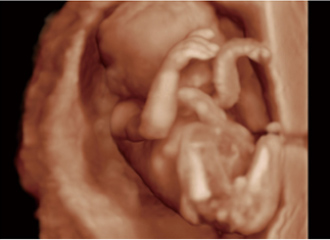

临床图像